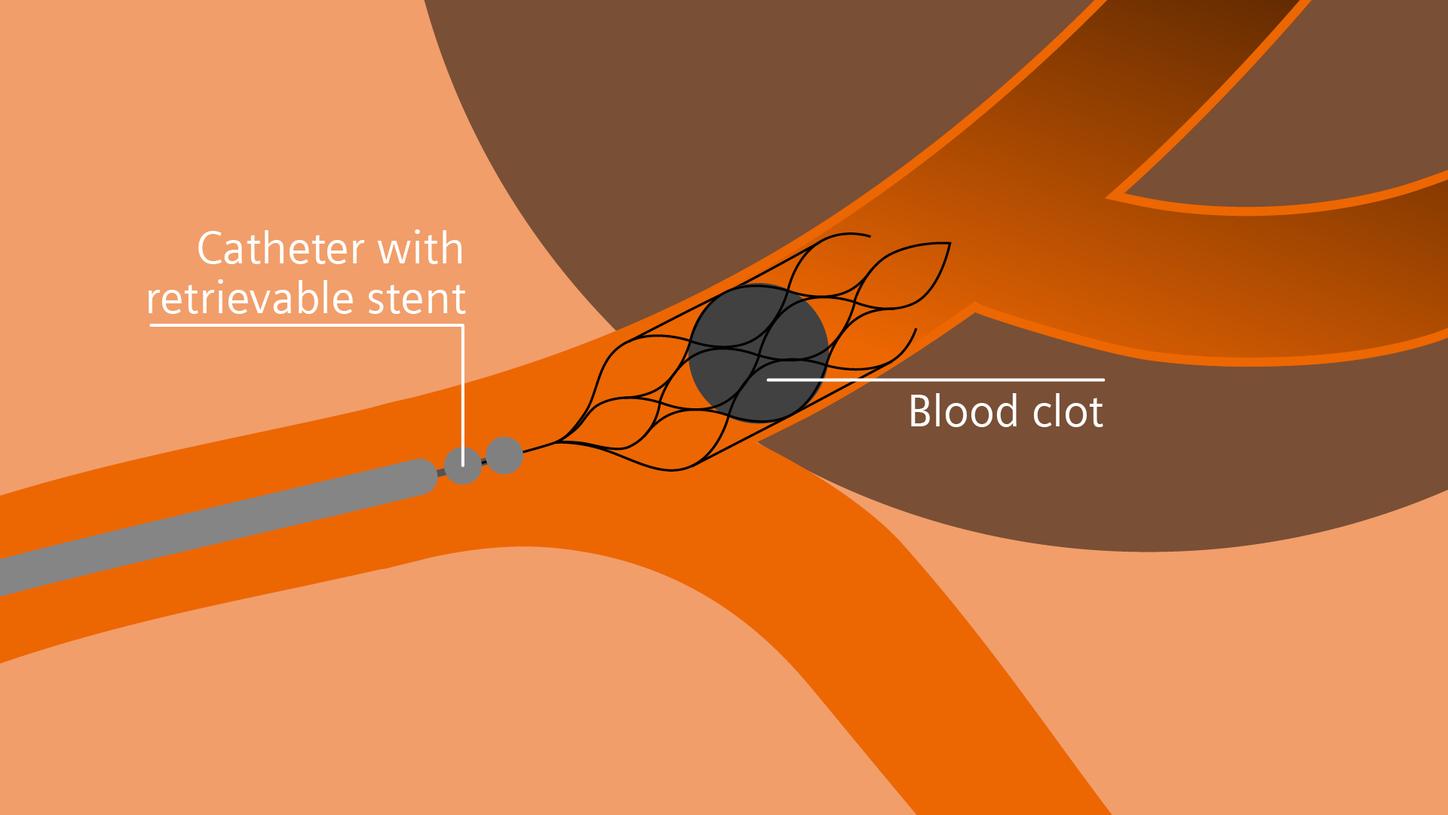

Treatment

In stroke care, time is brain. Rapid and accurate imaging is crucial to assess the extent of brain injury and guide immediate treatment. Angiography, MRI, CT, ultrasound, and lab diagnostics are essential tools in identifying stroke type, location, and severity. Advances in imaging technology now allow for even faster acquisition, improved resolution, and enhanced visualization of brain tissue and blood vessels. Innovations such as perfusion imaging, real-time vascular mapping, and AI-assisted diagnostics are transforming stroke workflows and enabling precise, timely interventions.